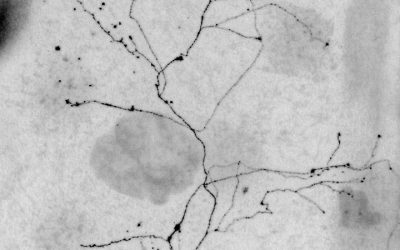

anabel.garciaOn November 20th, our Peripheral Neuropathies team at IDiBE, led by Prof. Antonio Ferrer Montiel, participated in the #HealthResearch Ceremony 2025 held at CosmoCaixa Barcelona, where we received...